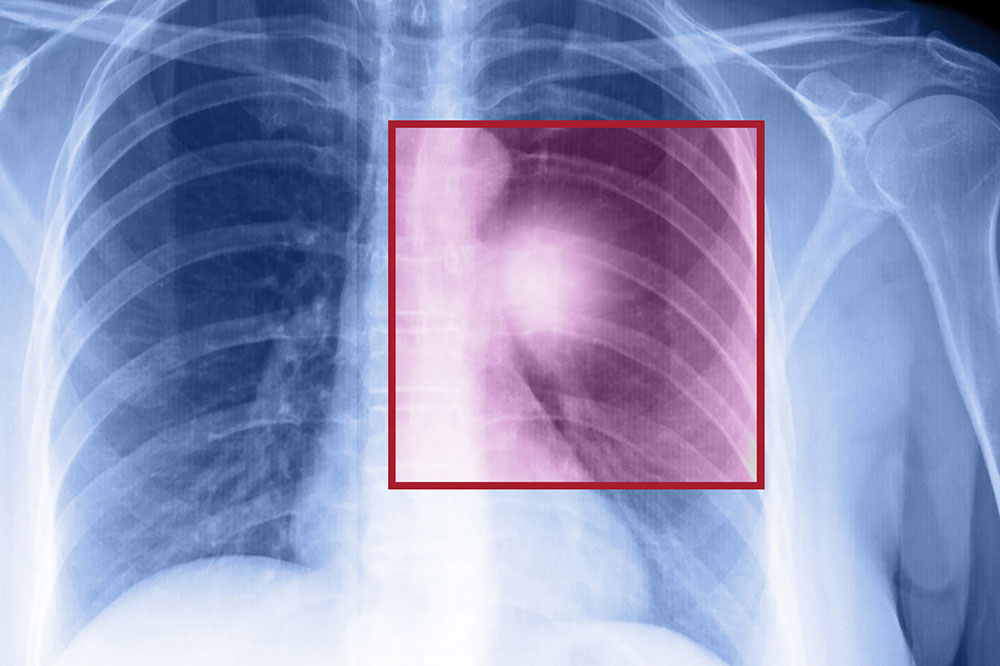

Lung cancer – Types, symptoms, and causes

When the cells in the lungs begin to abnormally multiply and grow, it results in cancer. Lung cancer is one of the leading causes of death in the world. And the risk of suffering from this life-threatening disease is even higher when one is a smoker. Herein, we discuss the various factors that come into play when it comes to lung cancer.